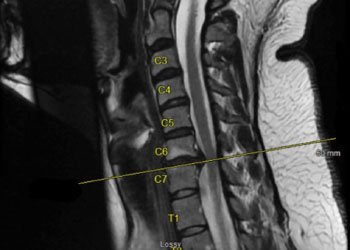

The patient is a 65-year-old woman with a history of hypertension and hypercholesterolemia who was experiencing bilateral lower extremity weakness and numbness for close to one […]